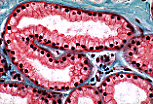

| 肌上皮细胞位于腺细胞基底部与基膜之间,形成一层梭形(长梭形)细胞。 其细胞质呈嗜酸性,细胞核致密。 在这张 外泌汗腺 分泌单位切片中(柱状透明腺细胞), 可观察到肌上皮细胞的横切面和纵切面。 沿腺细胞基底部的切线切面可呈现肌上皮细胞的“斜切面(cavalière)”视野。 | |

| 这是人体腋窝处 顶泌汗腺(假顶泌汗腺) 分泌单位周围的肌上皮细胞 (可通过宽大的管腔、高立方形细胞层识别,部分细胞顶端呈球状隆起), 其形态特征与外泌汗腺中的肌上皮细胞一致。 | |